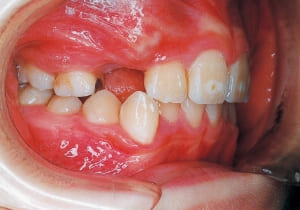

Age at initial visit : 7 y 7 m, male /Protruding upper bite. Open bite. Receding lower jaw. Protruding dual dentition.

3 Initial Visit 2-11-’88

4 Initial Visit 2-11-’88

The Class II condition is pronounced, with a significant overjet of 12.5 mm(3). Although the teeth size are large, crowding is relatively mild. The maxillofacial structure has good depth and a robust bone framework(5). The mandible itself is solid , robust gonial angle, but there is significant anterior-posterior displacement relative to the maxilla(ANB 10.0°). While there is no confirmed history of thumb-sucking or similar habits, the lower lip is already pushing up against the maxillary incisors. The cause of this condition is unknown.